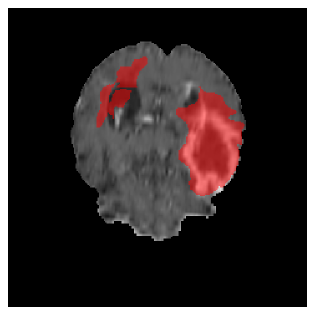

Appendix A Qualitative results

Figures 4 and 5 present the segmentation results for a patient from the BRATS dataset, visualized on a randomly selected slice. Figure 4 illustrates how tumor segmentation evolves over multiple episodes in S1 across different approaches including cumulative, naive, our approach, and the best buffer-free strategy (SI, =2). The cumulative approach, which trains on all encountered datasets together, maintains segmentation consistency across episodes but introduces significant amounts of false positives, particularly in the upper left area of the brain images. These misclassifications highlight its inability to generalize well across datasets despite access to all previous data. The naive approach, which learns sequentially without any continual learning strategy, suffers from severe catastrophic forgetting. While it initially segments well, performance deteriorates over episodes, leading to a near-complete loss of segmentation capability by the final episode. The SI (=2) approach, a regularization-based buffer-free CL strategy, performs reasonably well in early episodes but shows a significant performance decline over time. By the last episode, much of the tumor was no longer segmented, indicating difficulty in retaining prior knowledge. In contrast, our proposed approach initially produces more false positives but progressively refines its segmentation. By the final episode, it accurately retains the tumor region while minimizing misclassifications, demonstrating strong knowledge retention and adaptability across episodes. This suggests that our approach effectively mitigates catastrophic forgetting while maintaining segmentation performance over sequential learning.